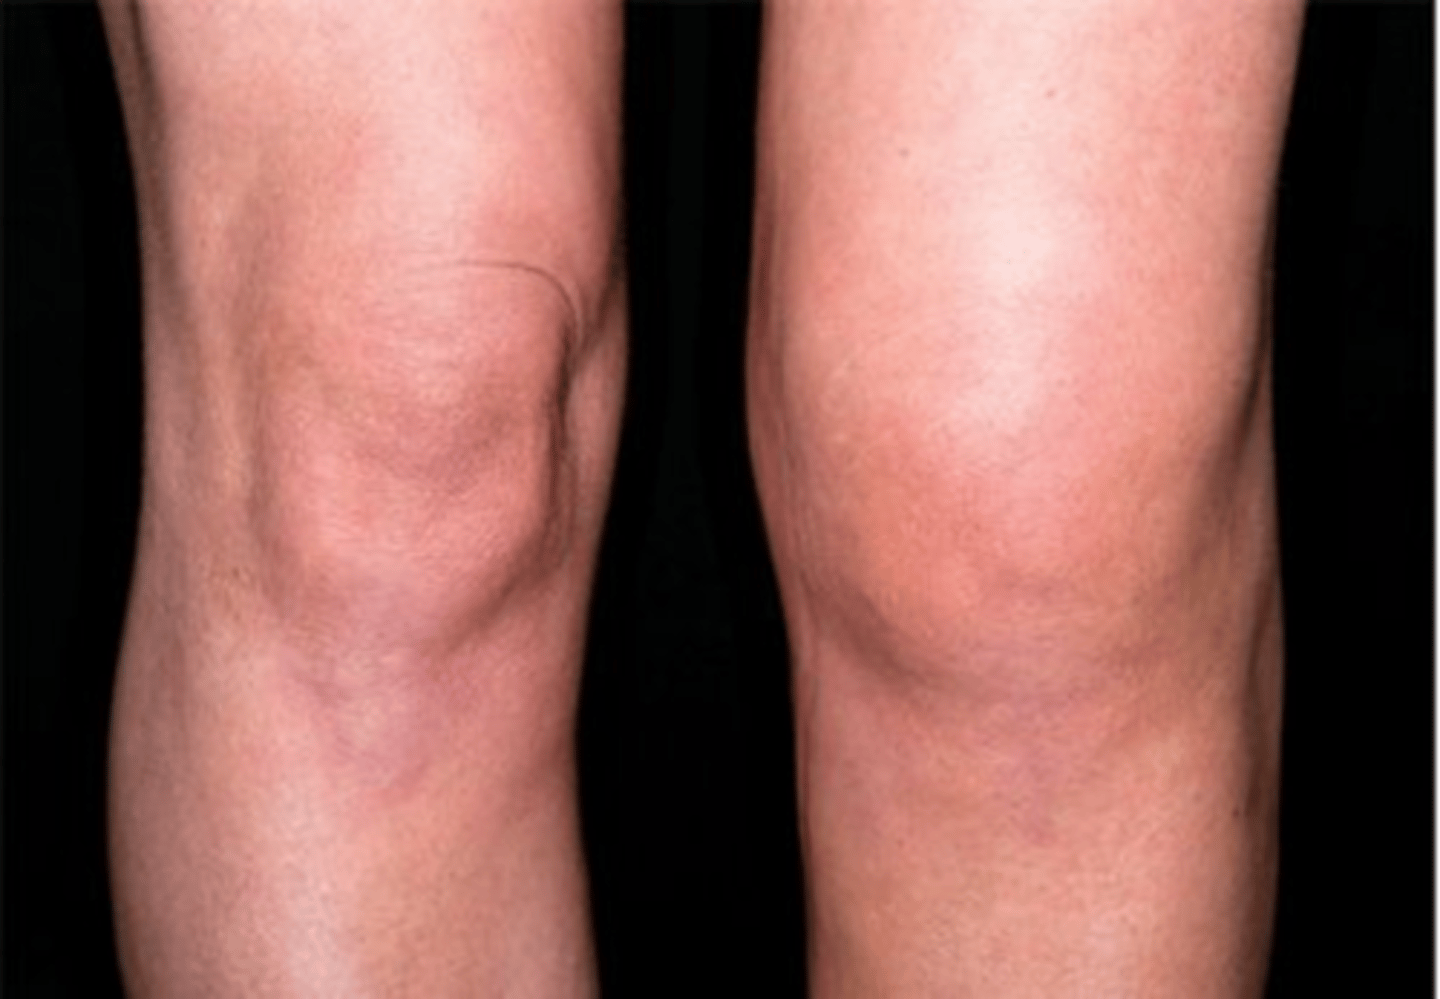

Swelling

OA on left hip